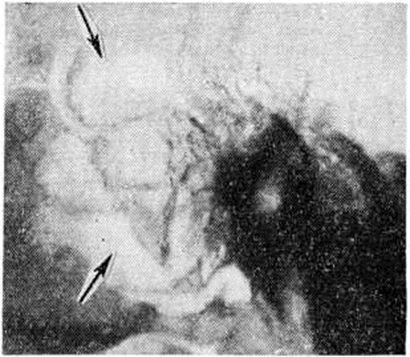

Рис. 3.

Рентгенограмма височной кости больного с гнойным мастоидитом в боковой проекции: в сосцевидном отростке виден большой дефект костной ткани (указан стрелками).

Классическим методом рентгенологическое исследования сосцевидного отростка является предложенная Шюллером (A. Schuller, 1905) рентгенография височной кости в боковой проекции (рисунок 1), а также предложенная Стенверсом (Н. W. Stenvers, 1928) рентгенография сосцевидного отростка в косой проекции (рисунок 2). Рентгенологические картина начальной экссудативной стадии острого Мастоидит характеризуется только затемнением сосцевидных ячеек; симптомы нарушения костной структуры отсутствуют. Резкое понижение воздушности ячеек приводит к снижению естественной контрастности снимка и затрудняет выявление тончайших костных перекладин между ячейками височной кости. В пролиферативно-альтеративной стадии Мастоидит с выраженным разрушением перекладин сосцевидных ячеек на рентгенограмме обнаруживается значительная потеря интенсивности линейных теней перекладин, а местами почти полное их отсутствие. При гнойном расплавлении перекладин и образовании абсцесса в сосцевидном отростке определяется очаг разрежения костной ткани. Очаг костной деструкции некоторое время может сохранять на рентгенограмме трабекулярную структуру, что объясняется наличием сохранившихся ячеек, окружающих полость абсцесса. При образовании субпериостального абсцесса с полным разрушением костной ткани просветление от деструктивного очага становится интенсивным и бесструктурным (рисунок 3). В период сохранения трабекулярности в области абсцесса, особенно небольшого, рентгенологическое распознавание его может представлять значительные трудности. Полость такого абсцесса в хорошо развитом пневматическом сосцевидном отростке ясно видна на томограммах височной кости.